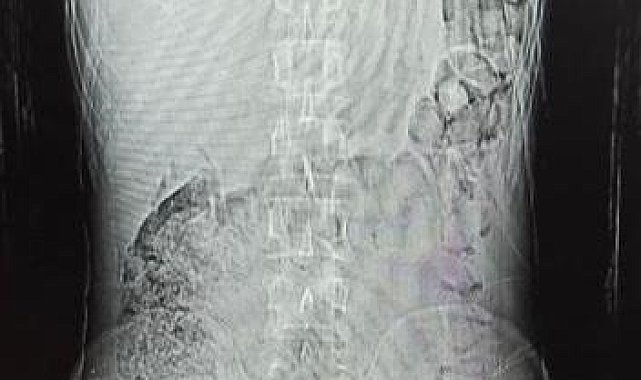

Edinilen bilgiye göre, Narkotik Suçlarla Mücadele ekiplerinin madde ticareti ve nakline yönelik yapılan çalışmalar sonucunda durumundan şüphelenilerek yakalanan ve uyuşturucu maddeleri yutarak nakletmeye çalışan İran uyruklu F.S. (30) yapılan iç beden muayeneleri sonucunda mide ve bağırsak kısmında 78 kapsül halinde 603,35 gr Afyon Sakızı ve 17 kapsül halinde 111,35 gr Metamfetamin maddeleri ele geçirildi.